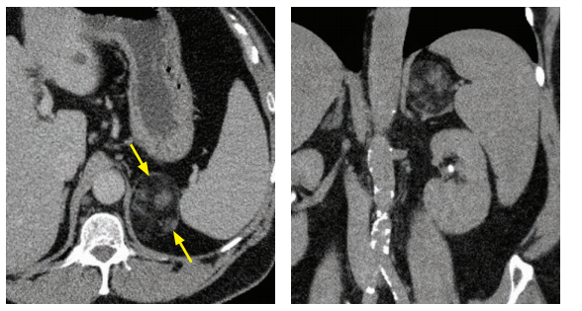

pheochromocytoma

pheochromocytomas arise from what cell type

chromaffin cells